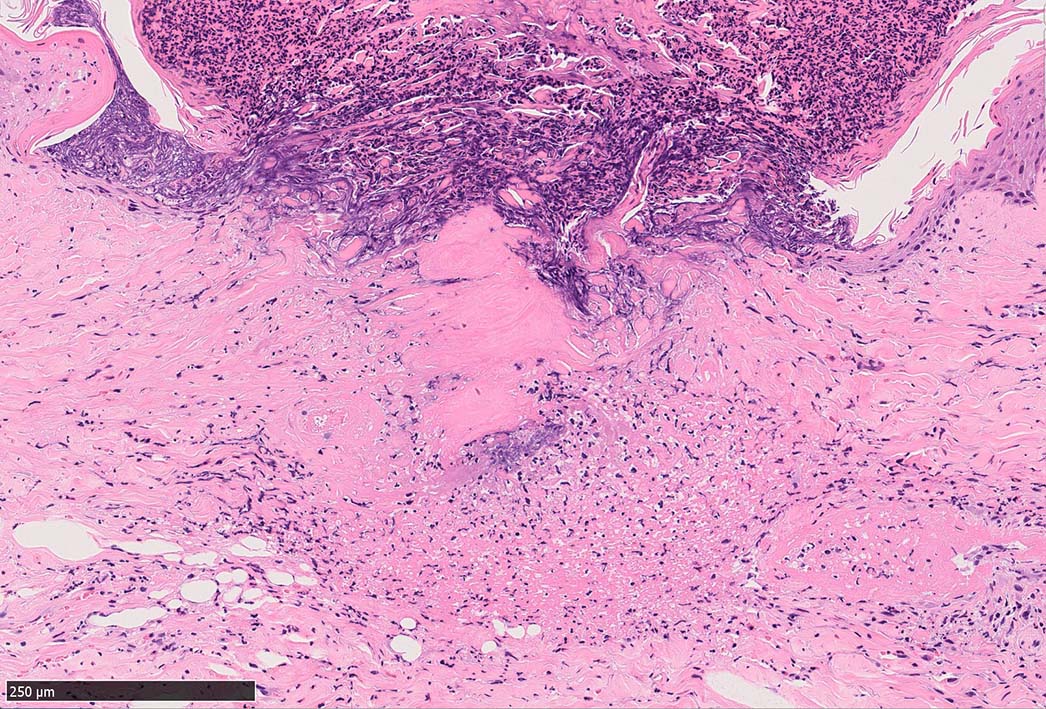

IWT-case03 マダニに咬まれた. 自分で虫体を除去したが傷がびらん化し, 発熱を来したため, 来院する.

痂皮の下に硝子様凝固物があり, 周囲には壊死組織が形成されている. 近傍の細血管には凝固物による閉塞の所見があるように見える. 連続する細血管には, fibrinoid necrosisを呈する壊死性血管炎が認められる.

セメント様物質を注入した後には抗凝固物質(抗トロンボキナーゼ活性因子,アピラーゼによる抗血小板活性など)を分泌して,血液の凝固を防ぐ。加えて,エステラーゼ,アミノペプチダーゼ,プロスタグランジンE2などの物質を含む唾液を分泌して局所の炎症,充血,浮腫,出血などを引き起こし,吸血をより容易にしている。さらに飽血が近ずくとセメントを溶解する成分を含んだ唾液を分泌して,虫体は宿主から離脱することができるようになる。